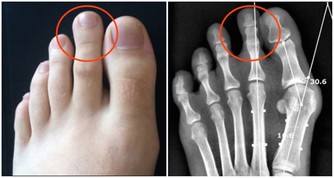

肝癌的發生並不是悄無聲息的,在肝癌發生初期,是有一定的症狀存在可以起到疾病的提示作用的。下面專家就肝癌的早期症狀做了介紹。 出血傾向:癌患者常有牙齦出血、皮下淤斑等出血傾向,主要是由於肝功能受損、凝血功能異常所致,它在肝癌合併肝硬化的患者中尤為多見。消化道出血 較為常見,主要是由於門靜脈高壓導致食管胃底 靜脈曲張 所致。事實上,消化道出血也是導致肝癌患者死亡的最主要原因。 下肢水腫:肝癌伴腹水的患者,常有下肢水腫,輕者發生在踝部,嚴重者可蔓延至整個下肢。臨床上曾見到有的患者下肢高度水腫,水液能從大腿皮膚滲出。造成下肢水腫的主要原因是腹水壓迫下肢靜脈或癌栓阻塞,使靜脈回流受阻。輕度水腫亦可因血漿白蛋白過低所致。 文章導讀